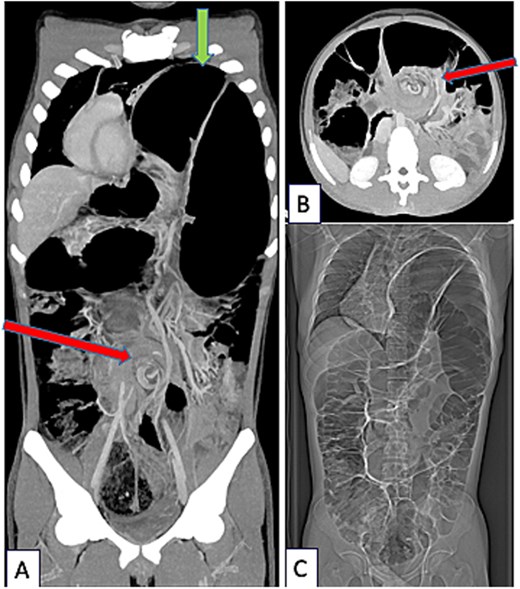

An 18-year-old male originally from Egypt presented to the emergency department with severe abdominal pain suggestive of bowel obstruction. Over the preceding 10 days, he had experienced recurrent non-bilious vomiting, and bowel movements had ceased for 48 h. Since childhood, he had suffered from frequent constipation and had developed chronic abdominal pain during the past year. He had never engaged in sports, particularly endurance activities, and had taken no chronic medication other than laxatives. Physical examination revealed a markedly distended abdomen and absence of breath sounds on the left side. Contrast-enhanced chest and abdominal computed tomography (CT) demonstrated a mesentero-axial sigmoid volvulus with a characteristic “whirl sign,” without evidence of perforation (Fig. 1A and B). The most distended segment of colon had migrated into a large left diaphragmatic eventration, causing mediastinal shift and complete left lung atelectasis (Figs 1C and 2A). Laboratory tests showed no inflammatory response. Under general anesthesia, an initial bedside endoscopic decompression achieved partial detorsion, requiring a second successful endoscopic procedure. Owing to the presence of megacolon and marked mesenteric laxity, the risk ofrecurrence remained high, and surgical management was indicated. Due to organizational constraints, a two-step surgical strategy was adopted. First, an open sigmoidectomy with mechanical end-to-endcolorectal anastomosis was performed. Before thoracic correction, dynamic thoracic magnetic resonance imaging confirmed persistent massive eventration (Fig. 3A), with major mediastinal displacement and absence of contractile activity of the left hemidiaphragm. Pulmonary function tests showed an forced expiratory volume in one second at 71% of predicted (decreasing to 64% in the supine position) and a vital capacity of 74%. Two months later, diaphragm plication reinforced with prosthetic mesh was performed through a video-assisted lower lateral mini-thoracotomy. Intraoperative findings confirmed a massive eventration leaving minimal space for the compressed left lung (Fig. 3B). The diaphragm was extremely thin—~1 to 2 mm—appearing nearly transparent after incision (Fig. 3C). Postoperative recovery was uneventful, except for a transient functional bowel obstruction managed medically. Histopathologic examination of the resected colon ruled out Hirschsprung disease and revealed chronic ischemic changes with fibrosis separating the external muscular layer (Fig. 3D). Four months after the final procedure, the patient showed clear clinical improvement, with normalized bowel habits and the ability to climb several flights of stairs without dyspnea. Chest X-ray confirmed left lung re-expansion and mediastinal repositioning (Fig. 2B). Chronic colonic distension persisted without symptoms and exerted mild upward pressure on the repaired left hemidiaphragm.

(A) Chest X-ray done when acute sigmoid volvulus occurred, revealing the major diaphragmatic eventration causing severe contralateral mediastinal shift and complete left lung atelectasis. (B) Chest X-ray done 4 months after sigmoidectomy and diaphragm plication. The left lung is well reexpanded and the mediastinum is in good position. The left hemidiaphragm is stabilized at a correct but high level because of persistent megacolon despite sigmoidectomy.